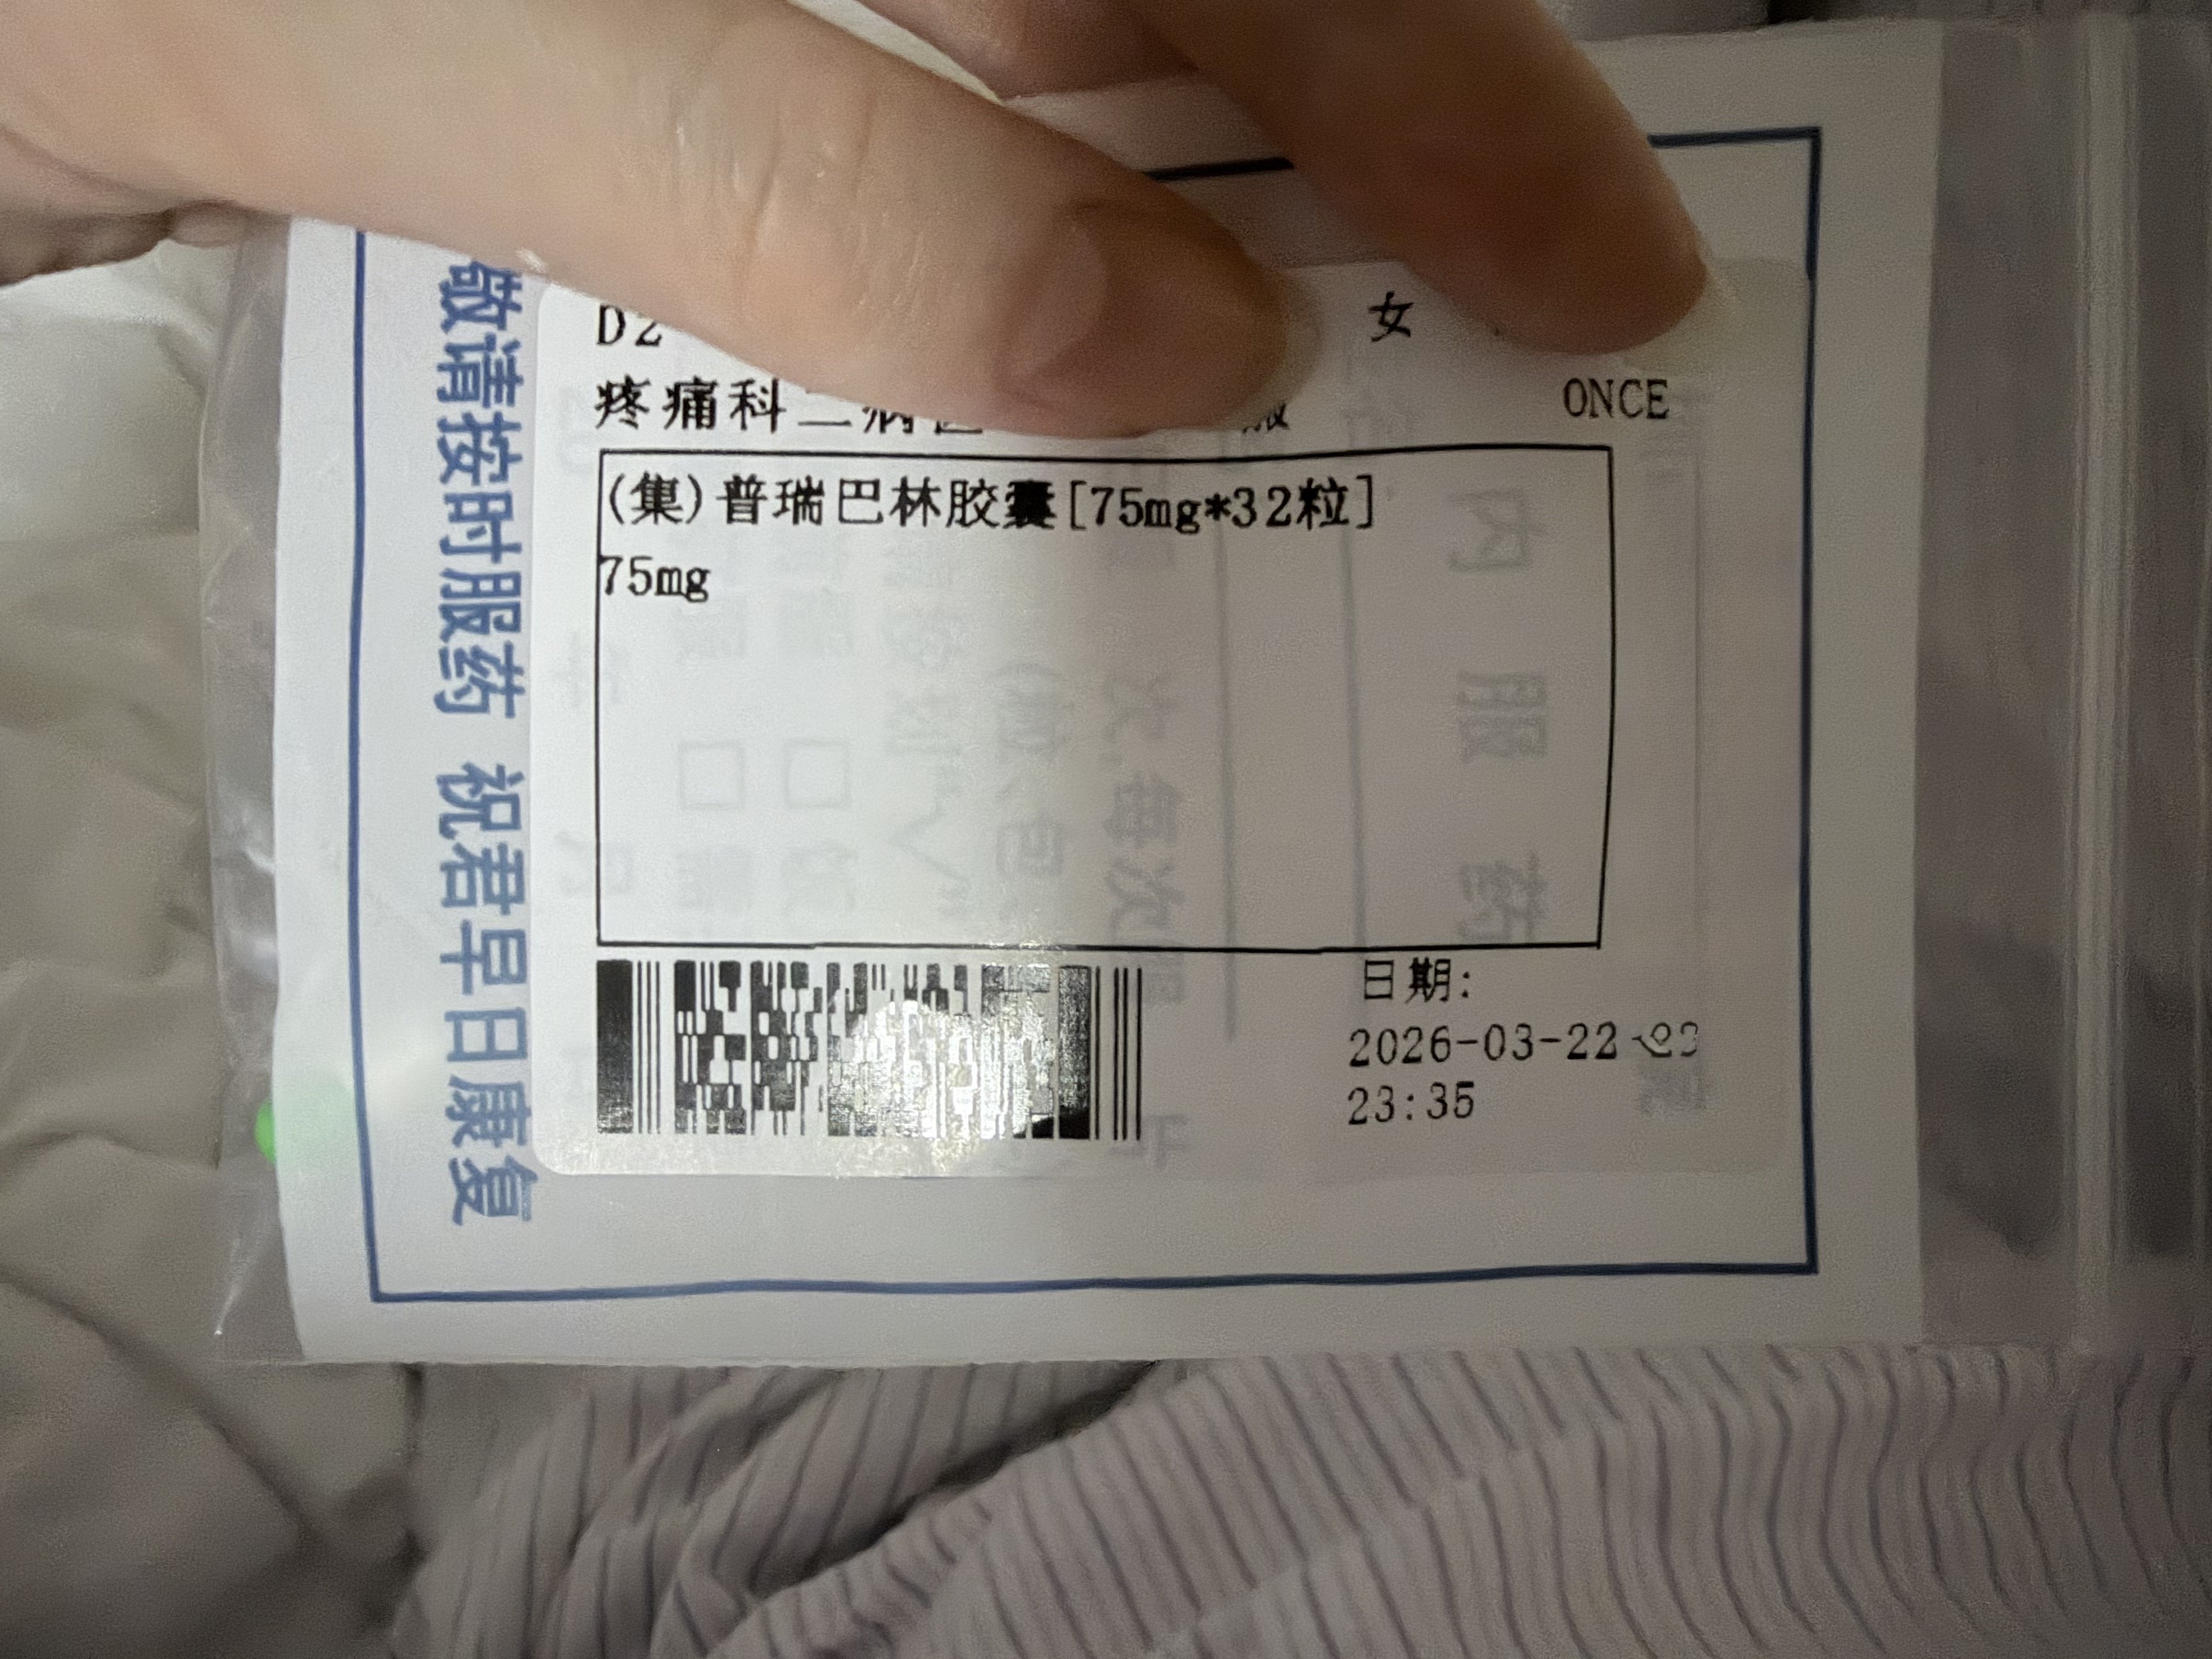

找值班医生护士开药,因为平常自己吃的没带过来,优先就考虑了曲马多(口服/注射),我说和我抗抑郁药cyp2d6冲突了

炽烈已极 @AnIncandescence我说不用那么强的也可以,医问加巴喷丁?我说弱了……于是目的达成,开了pr75

2026-03-22 15:58:58 UTC

虽然我吃这点可能没什么效果,但出院的时候说不定能开医嘱开处方甚至带药,处方有希望了!

炽烈已极 @AnIncandescence两年了,第一次正规途径吃到/开到普瑞…